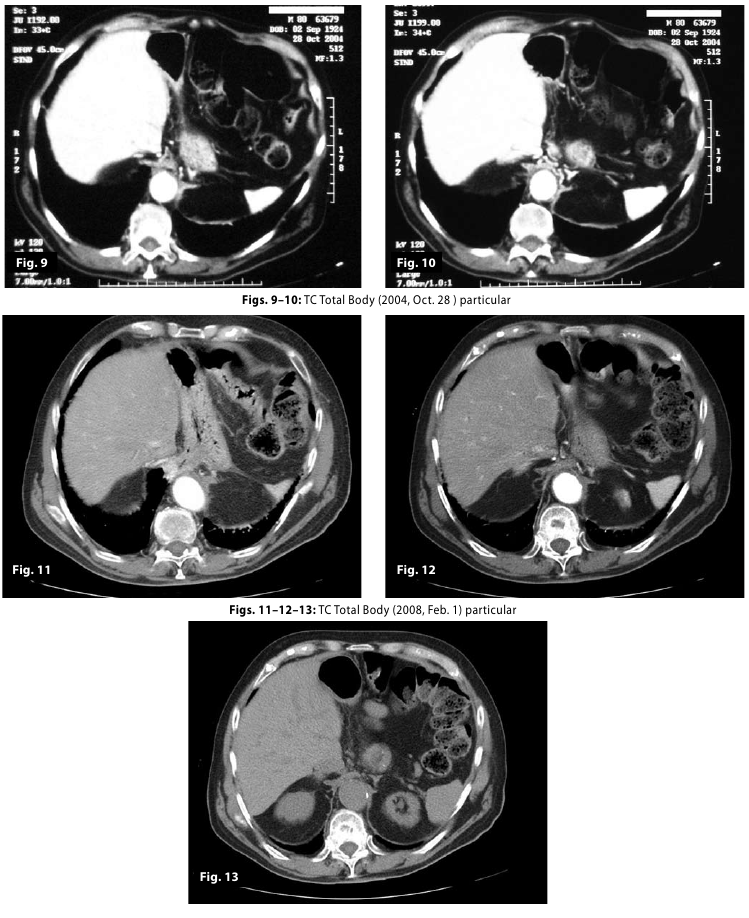

Figure9-10-11-1...